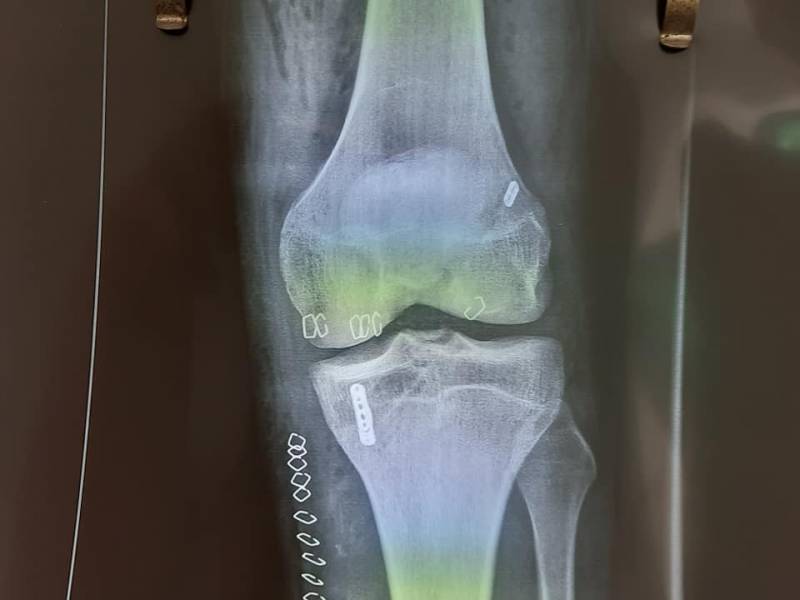

Γράφτηκε από την ΕΛΕΥΘΕΡΙΑ OnlineΓια πρώτη φορά πραγματοποιήθηκε στην Ορθοπαιδική Κλινική του Νοσοκομείου Κυπαρισσίας την περασμένη Παρασκευή αρθροσκοπική συνδεσμοπλαστική προσθίου χιαστού με μέθοδο all inside in technique with adgustuble button.

Αναφερόμενος στη συγκεκριμένη μέθοδος ο κ. Νταβέλης σημειώνει: «Η μέθοδος αυτή είναι ελάχιστα τραυματική για τις αυξητικές πλάκες σε ασθενή 18 ετών χρησιμοποιώντας σαν μόσχευμα μόνο τον ημιτενοντώδη από τους hamstrings. Με 24 ώρες νοσηλεία, μόνο, ο ασθενής βαδίζει με πλήρη φόρτιση χωρίς πόνο και πατερίτσες. Ενα μεγάλο ευχαριστώ τόσο στο νοσηλευτικό όσο στο ιατρικό προσωπικό του Ν.Μ. Κυπαρισσίας για την επιστημονική μα προπαντός ηθική υποστήριξη τους στην Ορθοπαιδική Κλινική».

Ο γιατρός τόνισε πως η συγκεκριμένη έγινε σε νεαρό 18χρονο ερασιτέχνη αθλητή και επιλέγεται για άτομα νεαρής ηλικίας. Υπογράμμισε δε πως τη μέθοδο που εφαρμόστηκε την έχει καθιερώσει ο Ιταλός γιατρός Τζουλιάνο Τσερούλι που πέρυσι είχε φιλοξενηθεί και ήταν το κεντρικό πρόσωπο σε ημερίδα που έχει διοργανώσει η Ορθοπαιδική Κλινική του Νοσοκομείου Κυπαρισσίας, με τη συμμετοχή πολύ σημαντικών επιστημόνων.